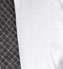

Caso clínico

Presentamos el caso de un paciente masculino de 61 años de edad, bruxista, con evidentes desgastes en toda la dentición y cracks de esmalte que pueden observarse en las fotografías iniciales de la primera visita (figuras 1 y 2). En las fotografías

Figuras 1 y 2. Imágenes intraorales de la primera visita donde se hacen evidentes diferentes desgastes en los dientes anteriores y a mayor detalle crakcs en el esmalte, así como lesiones por abfracción en los cuellos de los dientes de los premolares y caninos superiores.

laterales se ponen de manifiesto aún más varias lesiones de esmalte que indican la parafunción en el paciente, unido a los desgastes excesivos en varias zonas (figuras 3 y 4). El paciente acude por dolor y movilidad en la pieza 11, que se ha incrementado en los últimos días, además de sensación de “diente crecido” que como podemos ver en las fotografías iniciales es real, ya que el diente se encuentra ligeramente extruido en relación con el contralateral. Estos signos parecen indicarnos una fractura o fisura. En la fotografía oclusal, podemos observar el desplazamiento del diente debido a la movilidad (figura 5). Posteriormente se realiza un sondaje positivo de la pieza, que lleva a 11 mm por lo que se confirma la sospecha de fractura y se procede a la exodoncia del diente, realizándose una regeneración posterior del alveolo con PRGF-Endoret y

Figuras 3 y 4. Fotografías laterales donde se evidencian los cracks de esmalte en varios dientes y los desgastes excesivos en varios puntos. En estas imágenes se hacen más evidentes las lesiones por abfracción.